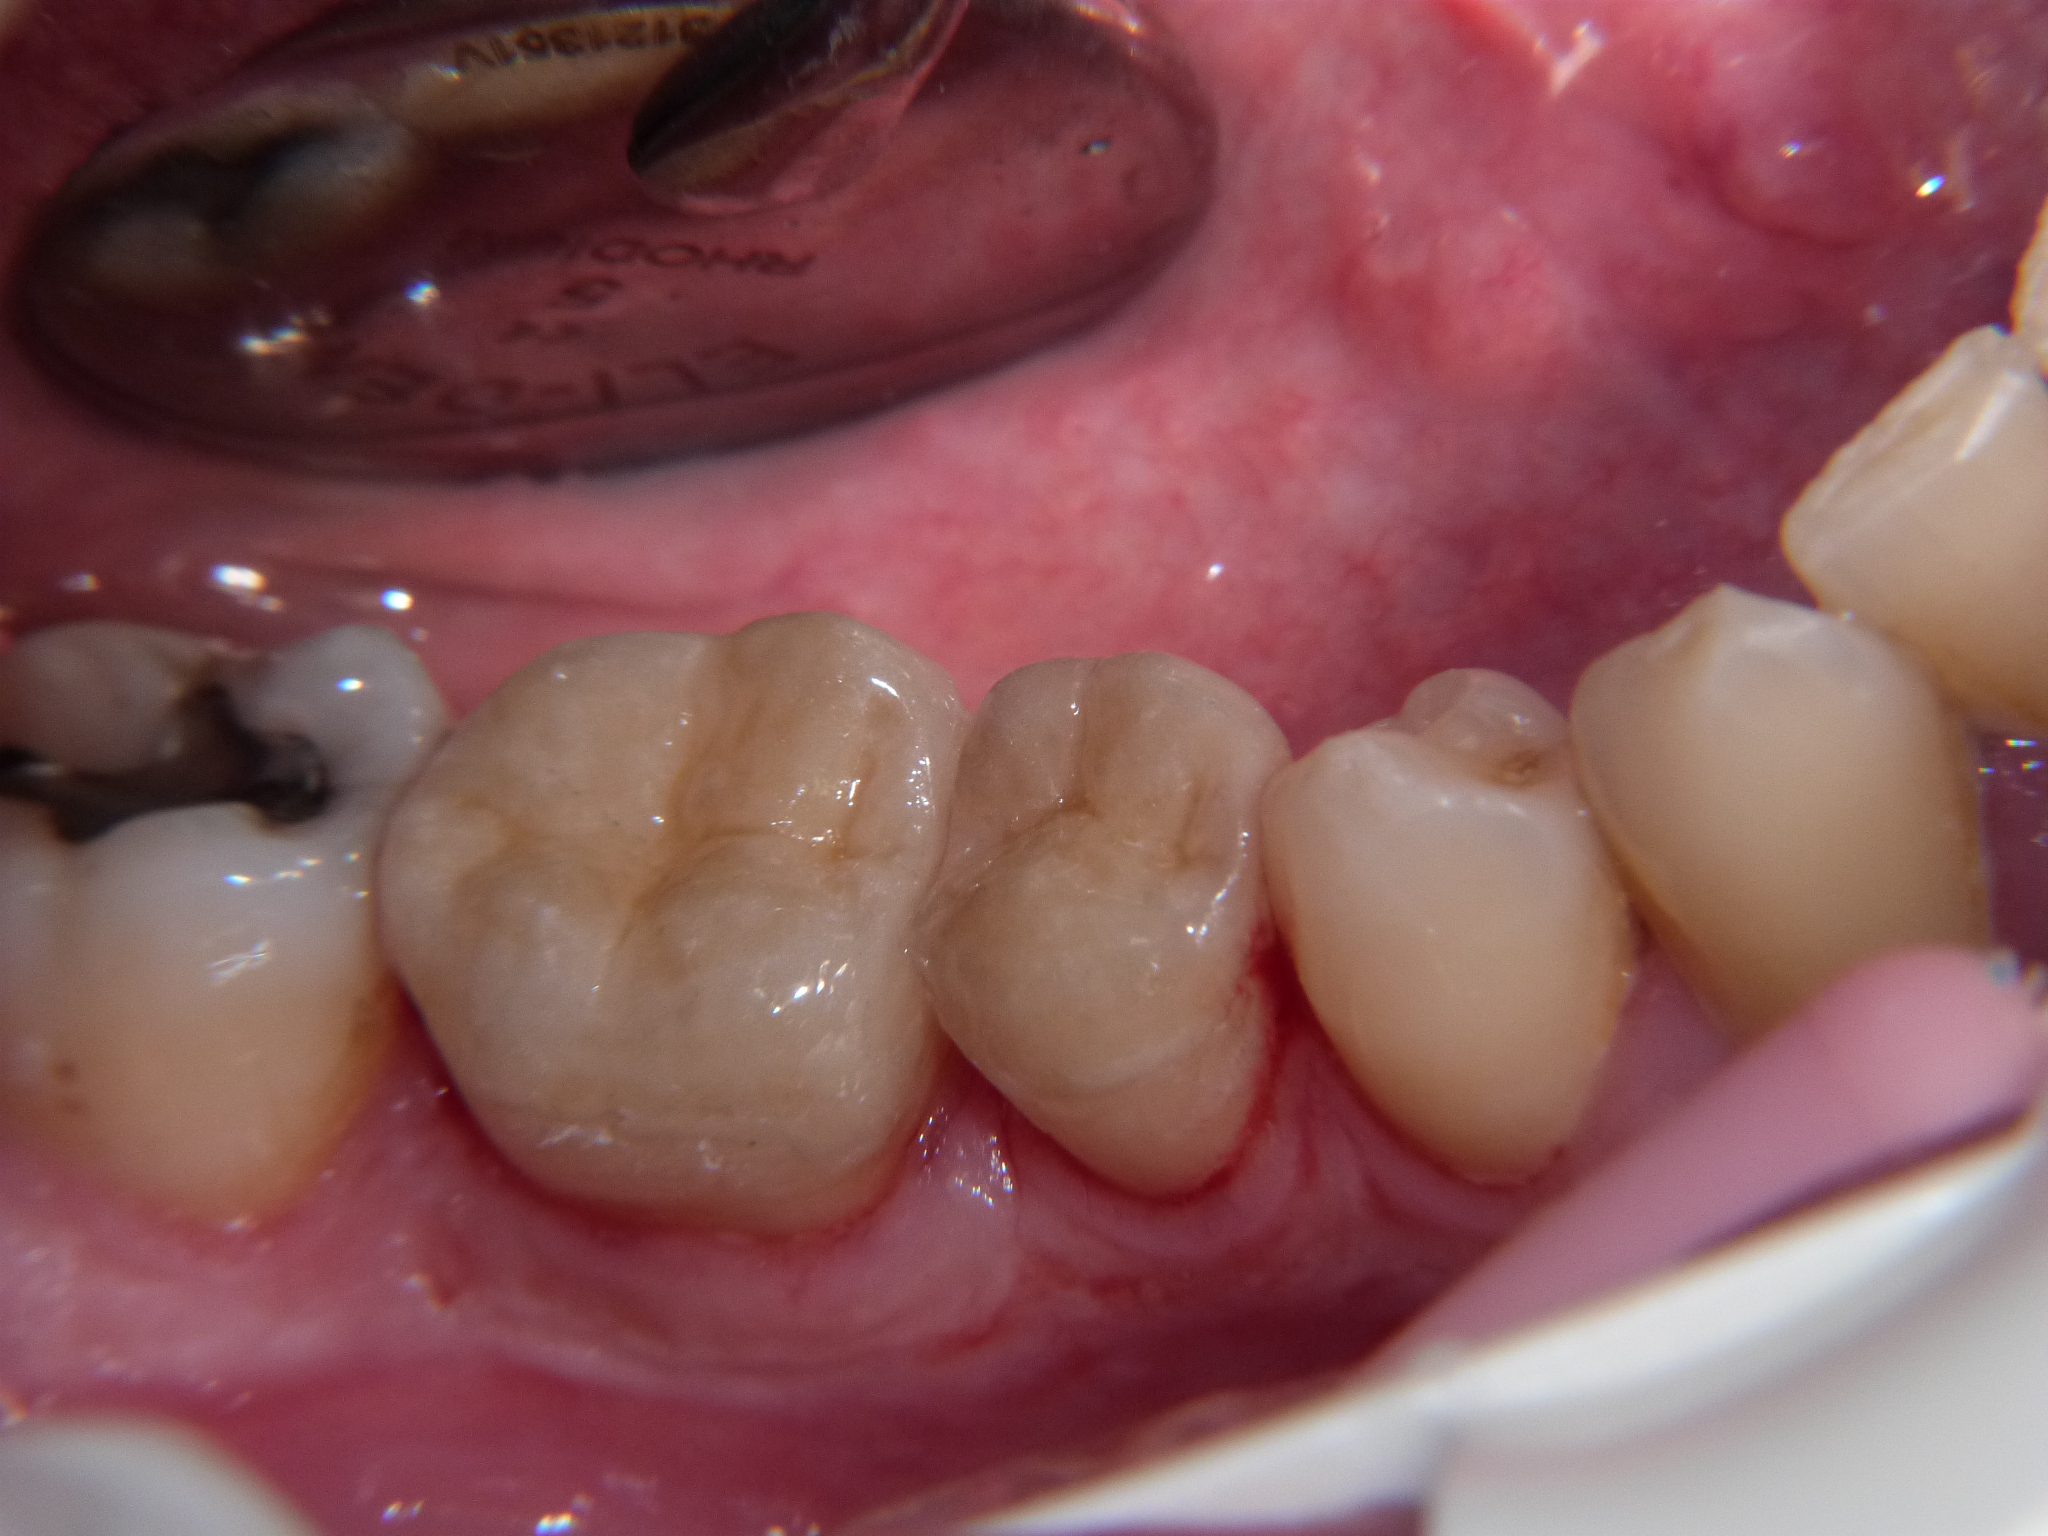

In questa sequenza di foto viene mostrato un caso clinico in cui si è scelto di riabilitare un 4.5 e un 4.6 trattati endodonticamente mediante due restauri indiretti di tipo overlay endo-crown realizzati in disilicato di litio ottenuto da pressofusione.

Fig 1 Elementi 4.6 e 4.5 al termine del trattamento endodontico